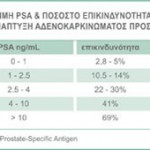

- Η ποσότης του "Ειδικού Προστατικού Αντιγόνου" στον ορό του αίματος (τιμή του PSA)

- Ο βαθμός ατυπίας των κυττάρων που πάρθηκαν από τη βιοψία βάσει της δεκαβάθμιας κλίμακας Gleason (Gleason Score)

- Η έκταση – στάδιο της νόσου σύμφωνα με τη διεθνή κλίμακα ΤΝΜ (Tumor – Nodes – Metastases)

Ο συνδυασμός των τριών παραμέτρων (PSA – Gleason score – TNMStage) κατατάσσει τους ασθενείς σε τρεις κατηγορίες, τους χαμηλής, μέσης και υψηλής επικινδυνότητας.

Ο συνδυασμός των τριών παραμέτρων (PSA – Gleason score – TNMStage) κατατάσσει τους ασθενείς σε τρεις κατηγορίες, τους χαμηλής, μέσης και υψηλής επικινδυνότητας.

Σε κάθε κατηγορία συνιστώνται ή αντενδείκνυνται κάποιες μέθοδοι αντιμετωπίσεως – θεραπείας.

- Χαμηλής επικινδυνότητας (Low Risk): Ασθενείς με PSA λιγότερο από 10 ng/ml (PSA<10), έχουν Gleason Score μικρότερο ή ίσο του 6 (Gleason <= 6) και είναι σταδίου T1 ή Τ2a.

- Μέσης επικινδυνότητας (Medium Risk): Ασθενείς με PSA από 10 – 20 ng/ml (PSA 10 – 20), έχουνGleason Score ίσο με 7 (Gleason = 7) και είναι σταδίου Τ2b.

Υψηλής επικινδυνότητας (High Risk): Ασθενείς με PSA μεγαλύτερο των 20 ng/ml (PSA > 20), έχουνGleason Score ίσο ή μεγαλύτερο του 8 (Gleason >= 8) και είναι σταδίου T2c, Τ3 ή Τ4.